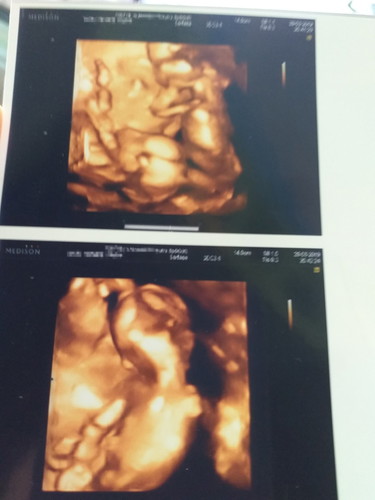

sharing janin kembar

Sharing dong bunda yg sedang hamil janin kembar, aku dah 15 weeks..kemaren usg sm dokter kt dokter semuanya alhamdulillah normal..doakan ya bunda smg diberikan kesehatan dan kelancaran persalinan dan dedek2 babynya selalu sehat

Aminn... Selamat ya bunn.. alhmdllh saya juga sedang hamil janin kembar skrng uk. 20wek semoga hamilnya di beri kelancaran aminn